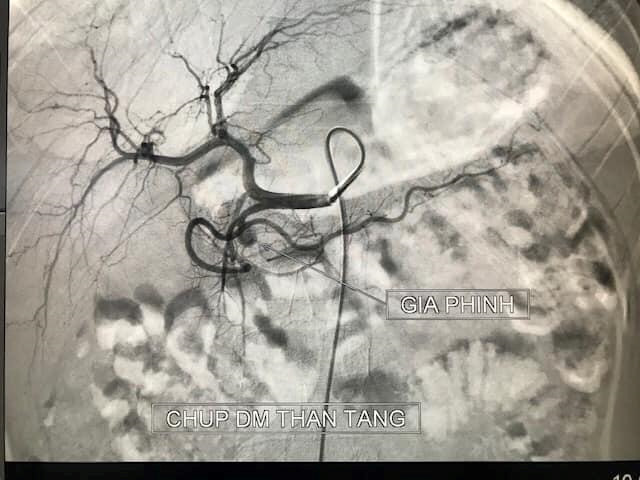

Hình ảnh ổ giả phình lớn động mạch vị tá tràng ở bệnh nhân

Khi vào viện, bệnh nhi này nôn máu nhiều lần không tự cầm. Phim chụp cắt lớp vi tính cho thấy ổ giả phình lớn động mạch vị tá tràng (có chức năng cung cấp máu cho tá tràng - tụy và dạ dày).

Sau 20 phút can thiệp với 5 nút coils, ổ phình đã được loại bỏ hoàn toàn. Bệnh nhi hết nôn máu, huyết động ổn, sau đó được chuyển về khoa Nhi tiếp tục điều trị.